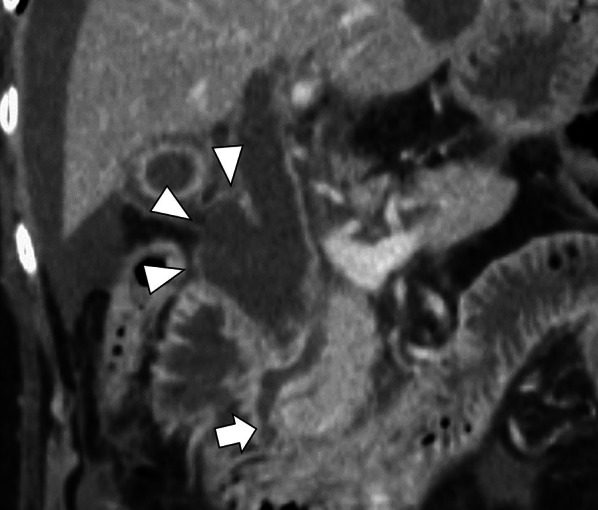

She had no history of past abdominal operations, and other past medical history included choledocholithiasis and pancreatitis. Hematological investigations on admission revealed coagulopathy, renal dysfunction, and circulatory insufficiency (Table 1), which indicated septic disseminated intravascular coagulation. Significantly high levels of serum transaminases, bilirubin, and pancreatic enzymes suggested a condition associated with biliary tract disease. As shown in Fig. 1, enhanced CT revealed that the supraduodenal CBD was markedly dilated similar to a diverticulum (arrow), and the bile duct wall had a partial defect in continuity (arrowhead). Moreover, the common channel of the pancreaticobiliary duct was long at 9.3 mm in length and seemed to be joined outside the muscular layer of the duodenal papilla (arrow) on the coronal CT view (Fig. 2). Eventually, we diagnosed biliary panperitonitis due to the spontaneous CBD perforation accompanied with congenital biliary dilatation and pancreaticobiliary maljunction. As her general condition improved following adequate primary resuscitation, she was able to undergo an emergency laparotomy to cure her septic peritonitis.